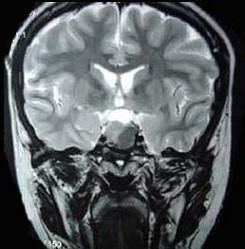

问题 男,47岁,视物模糊数月,头痛、恶心、呕吐3天,行MRI检查如图,最可能的诊断为()

选项 A.颅咽管瘤 B.脑膜瘤 C.蛛网膜囊肿 D.垂体瘤并出血 E.表皮样囊肿

答案 D